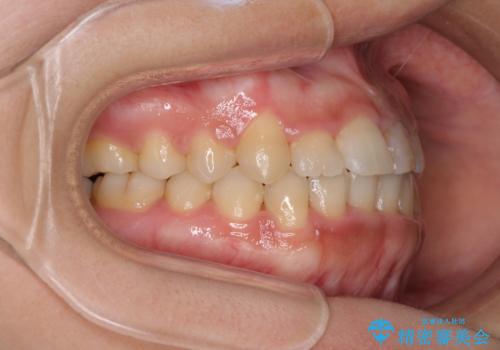

前歯の反対咬合 非抜歯のワイヤー矯正

- 前歯のでこぼこを気にして来院された患者様です。

1年半はかかると思っていた治療期間ですが、反対咬合となっている前歯が思いの外早く動き、僅か9ヶ月で終了させることができました。

前歯を気にせず笑えるようになり、患者様には大変満足していただきました。